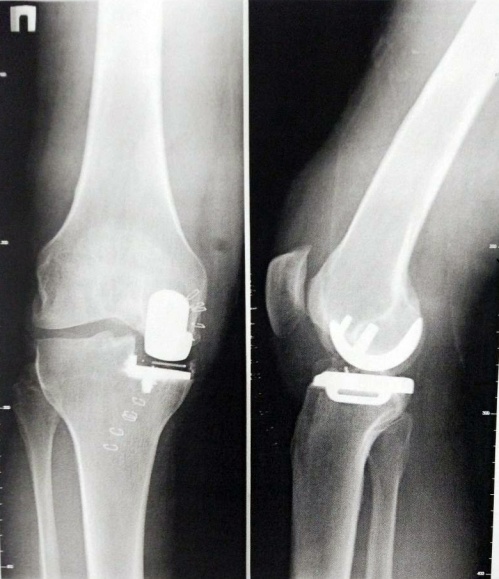

Замена коленного сустава необходима, когда происходит износ и разрушение сустава, что нарушает его функционирование. В 85% случаев показанием к проведению операции служит гонартроз третьей степени. При этой болезни гиалиновый хрящ изнашивается, развивается разрушение костей, образующих коленный сустав, деформация конечности. В результате возникает выраженный болевой синдром.

однополюсным, или частичным, — имплантатом заменяют только часть сочленения;

полным, или тотальным, — полностью удаляют коленный сустав, а на его место устанавливают эндопротез.